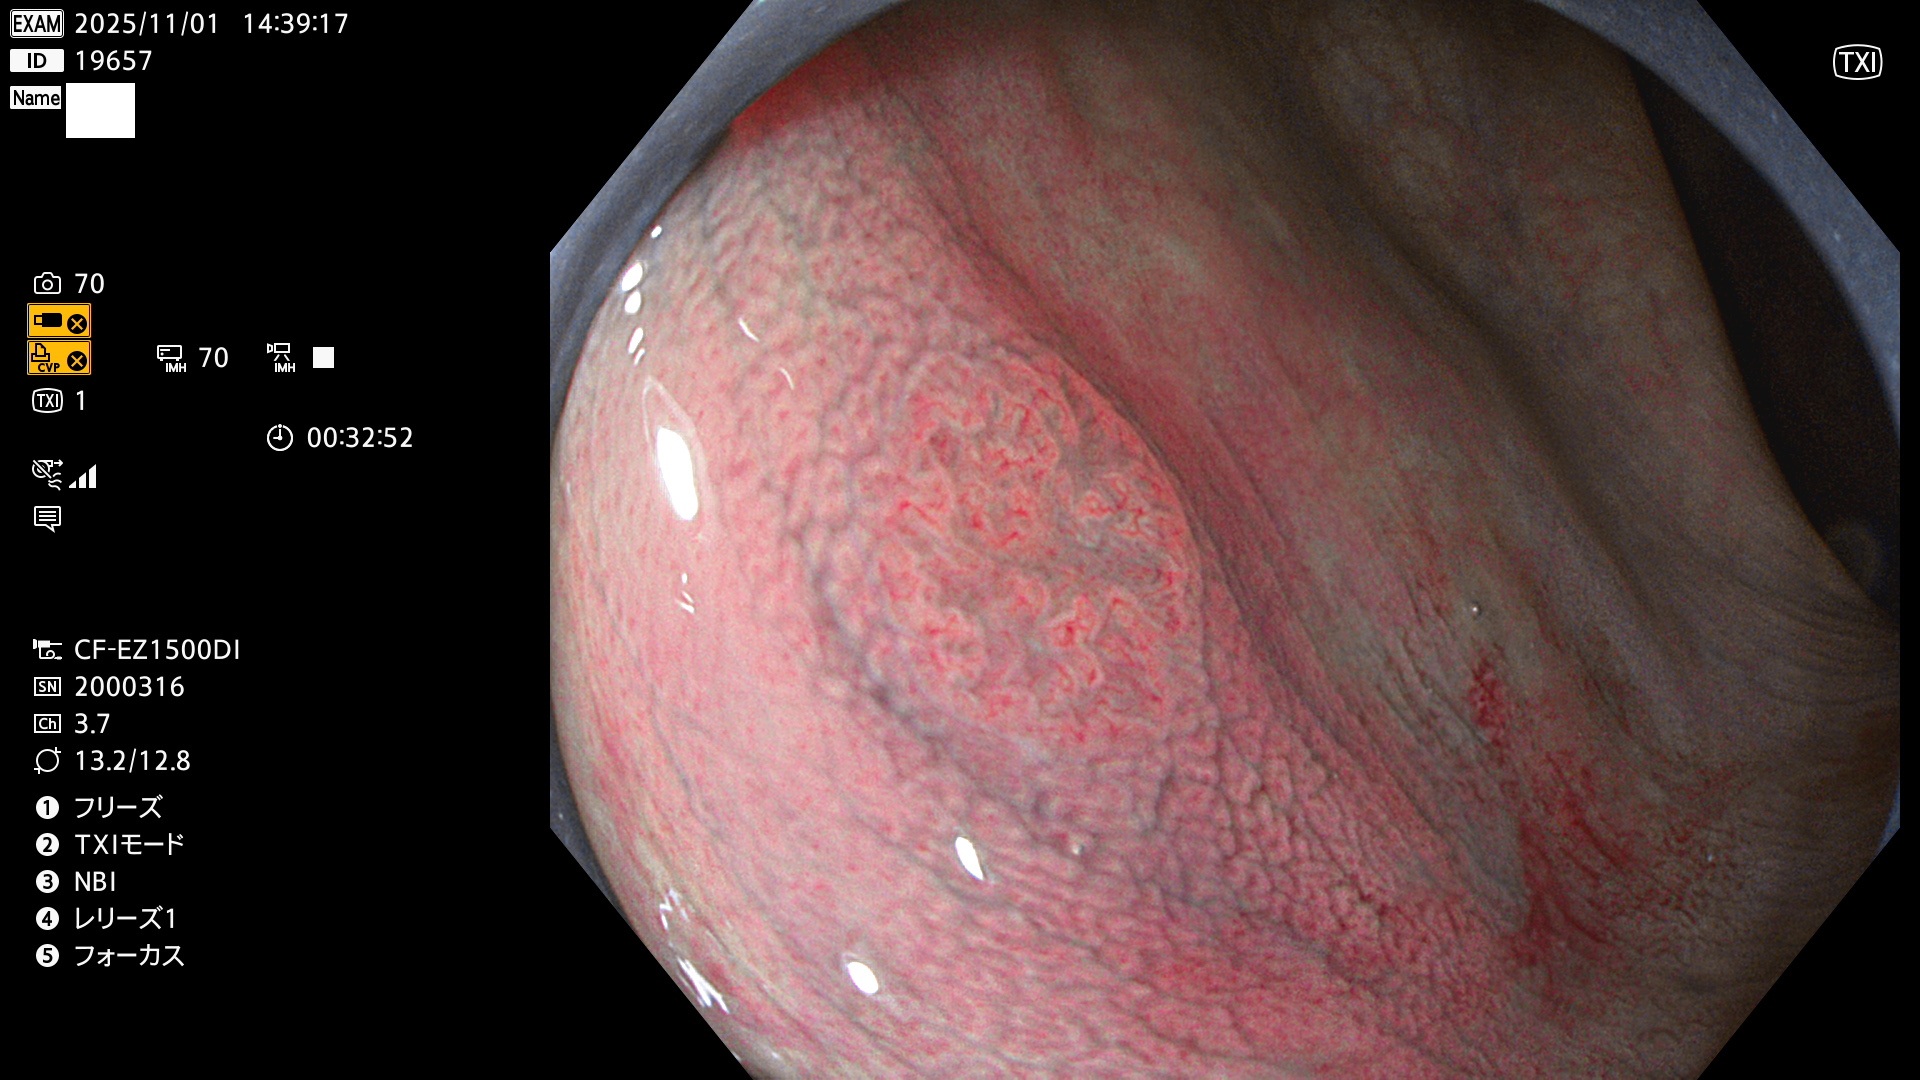

完全に平坦な物をUb、陥凹している物をUcと呼びます。Ubは認識が困難で、Ucはびらん(炎症)と紛らわしいために見落とされやすく、「内視鏡後・大腸癌」の原因になります。

毎週の検査(木・金・土・日)に発見されたUbとUc型・腺腫を、その週の日曜の夜にUPし1週間、提示します。

2025年10月30日〜11月2日の4日間(40件)9個 (Uc_ADR=9個/40人=23%)